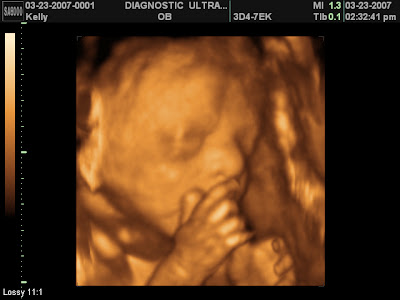

I had this 3d ultrasound about 5 weeks ago. The little peanut was just 26weeks old and he probably weighed around 2lbs at the time. When we first started the ultrasound he was sound asleep. It took 5 minutes of shaking/poking/and me turning side to side to get him to wake-up and turn around so we could see his face. He never opened his eyes for us, but he sure was active. We could see him playing with the umbilical cord, sucking his thumb (or at least trying), drinking the amniotic fluid, rubbing his face…and oh ya, grabbing his 'package' (yes, it is definitely a boy).

I love seeing his scrunched up little body.

Does this mean I have a thumb sucker already?